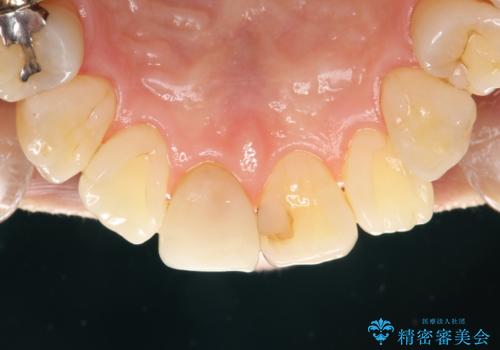

専門的な機械や材料を使用し、60分コースのPMTCクリーニングで、全体的な歯石や着色の除去を行いました。

PMTCは、毎日のブラッシングや食事によって傷ついた歯をツルツルでなめらかにします。継続して定期的に行うことで徐々に歯の表面の凸凹がツルツルになります。日常の飲食や、生活習慣スタイルにより、着色のつき具合には個人差があります。つきやすい方は月に1回のペースからPMTCを行い、徐々につきにくいお口の環境になってきたら3か月に1回のペースでPMTCを行うことがおすすめです。